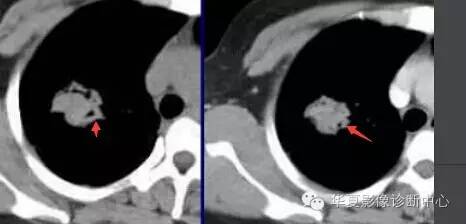

大家仔细看看这个中央不强化的腔内壁

你会发现内壁强化明显,边界清楚

一般这是炎性的脓腔,内层是肉芽肿,明显强化,分界清楚

癌肿的坏死一般是缺血性的,是肿瘤生长速度过快,中央带的血管受挤压,中央供血不足坏死的,一般边界模糊

内有内层强化,不会这么清楚

这是两者坏死的差异

内带强化带,边界清楚

但是这个其实整体看起来不是分叶征

只是一个一个的凸起